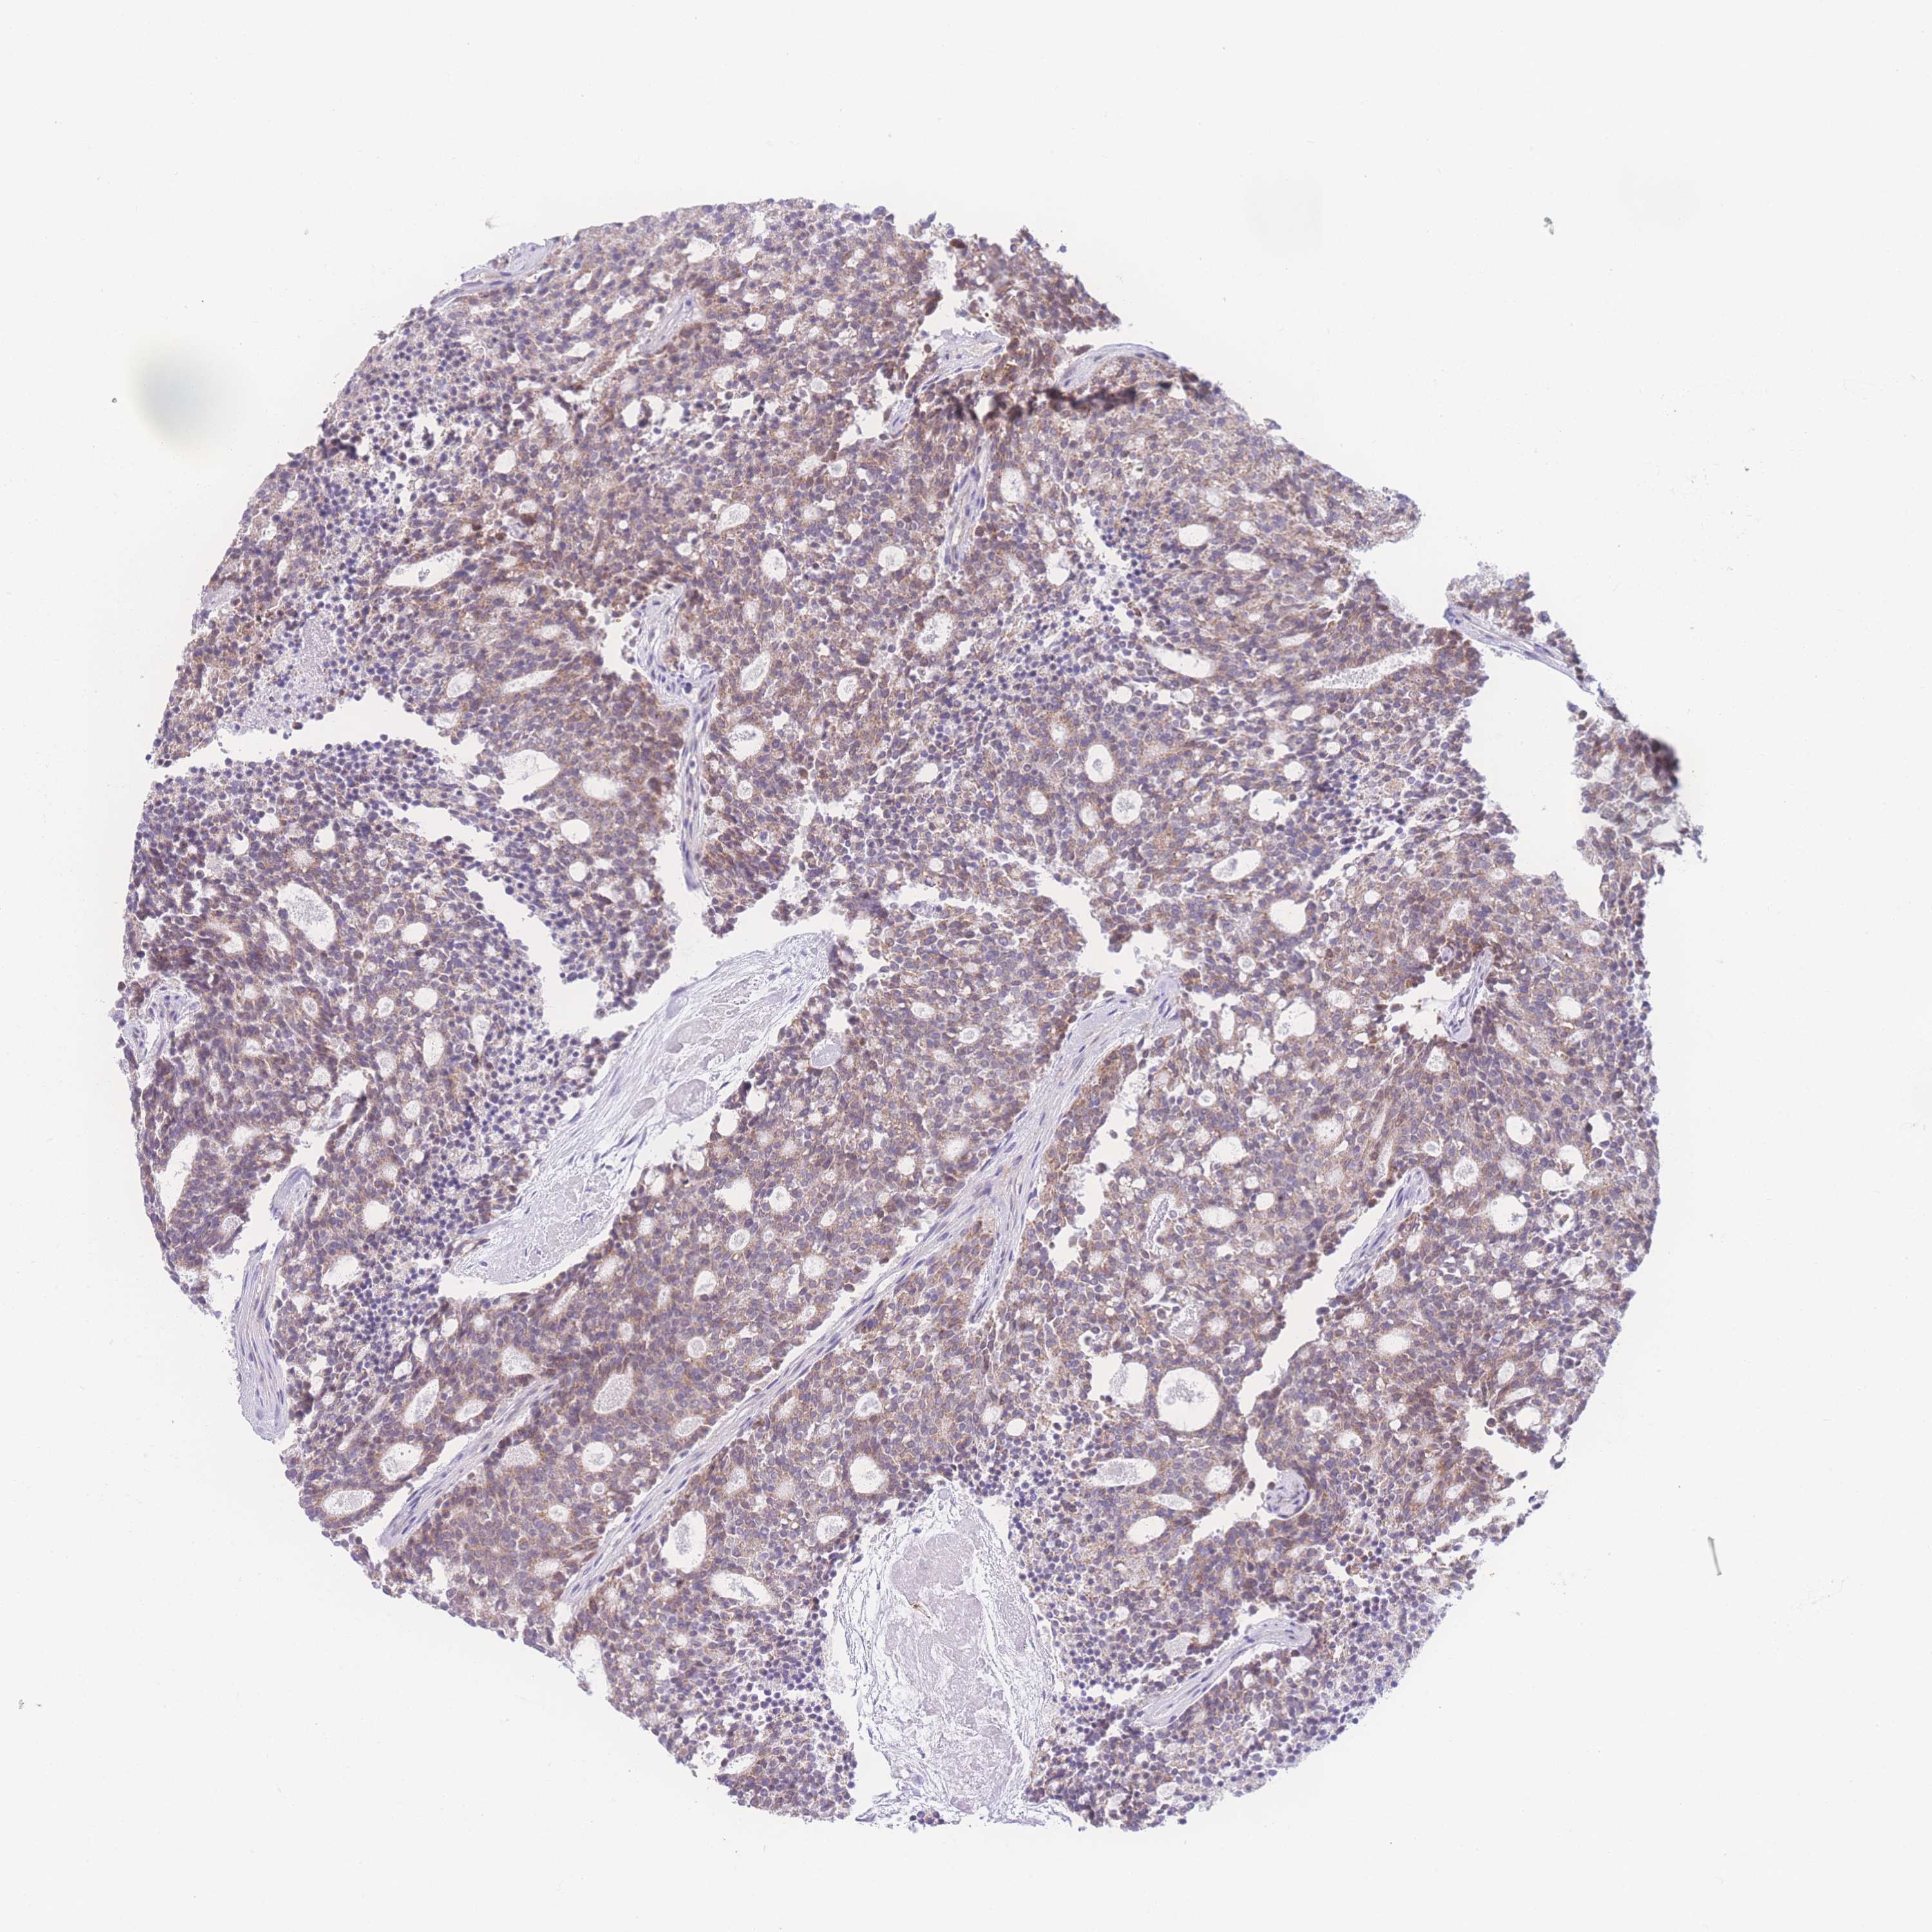

CARCINOID - Protein expressioni

A mouse-over function shows sample information and annotation data. Click on an image to view it in a full screen mode. Samples can be filtered based on level of antibody staining by selecting one or several of the following categories: high, medium, low and not detected. The assay and annotation is described here.

Antibody stainingi

Antibody staining in the annotated cell types in the current human tissue is reported as not detected, low, medium, or high, based on conventional immunohistochemistry profiling in selected tissues. This score is based on the combination of the staining intensity and fraction of stained cells.

Each image is clickable and will lead to virtual microscopy that enables deeper exploration of all samples and also displays staining intensity scores, fraction scores and subcellular localization as well as patient and tissue information for each sample.

Antibody HPA049189

Antibody HPA049447

Staining

High

Medium

Low

Not detected

Carcinoid, malignant, NOS

Carcinoma, NOS